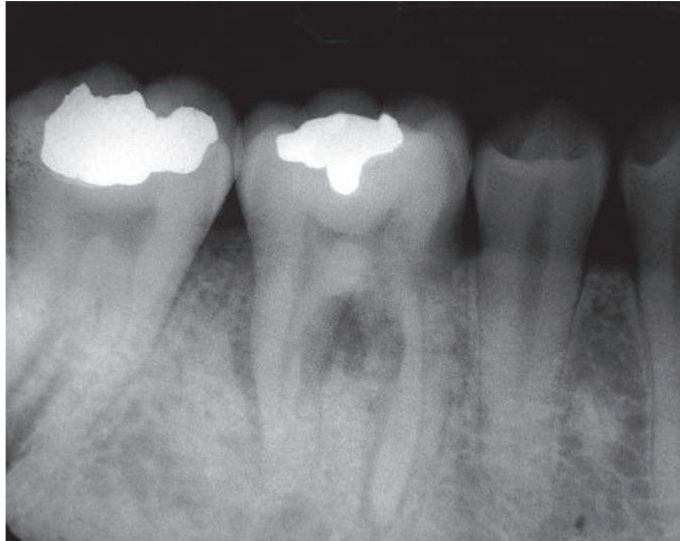

Osteosarcoma surrounding the roots of the first molar tooth. Note widened periodontal ligament.